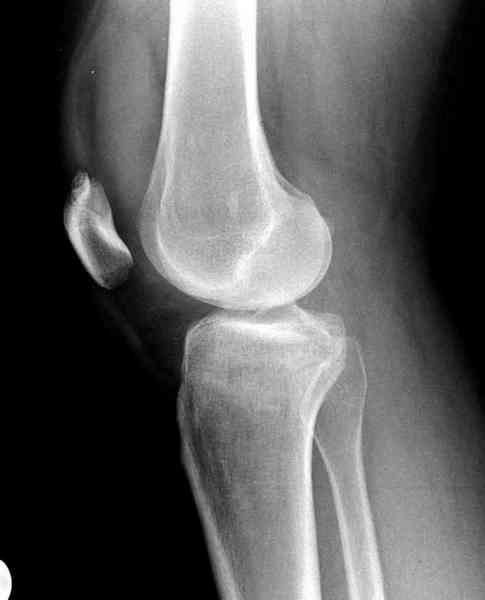

Как всегда прекрасная презентация. Совершенно согласен с необходимостью сохранять мениск и вообще согласен со всем, кроме одного. Фиксация должна проводиться после правильно выполненной репозиции. Главная цель репозиции - это восстановить высоту наружного мыщелка. В норме наружный мыщелок выше внутреннего на 4-5 мм на снимке в переднее заднем направлении АР.

Необходимость репозиции возникает при снижении высоты от 3 до 5 мм по разным источникам. По моему опыту 4 мм. Если не восстановить высоту мыщелка возникает вальгизация коленного сустава с относительным расслаблением передней крестообразной связки. При этом развивается нестабильность коленного сустава из-за недостаточности ПКС.

На представленном после операционном снимке нет репозиции, на что указывает низкое положение тибиального плато и перекрытие кортикальных пластинок в метафизарной части - указано стрелкой. Обычно чрескожную фиксацию я применяю